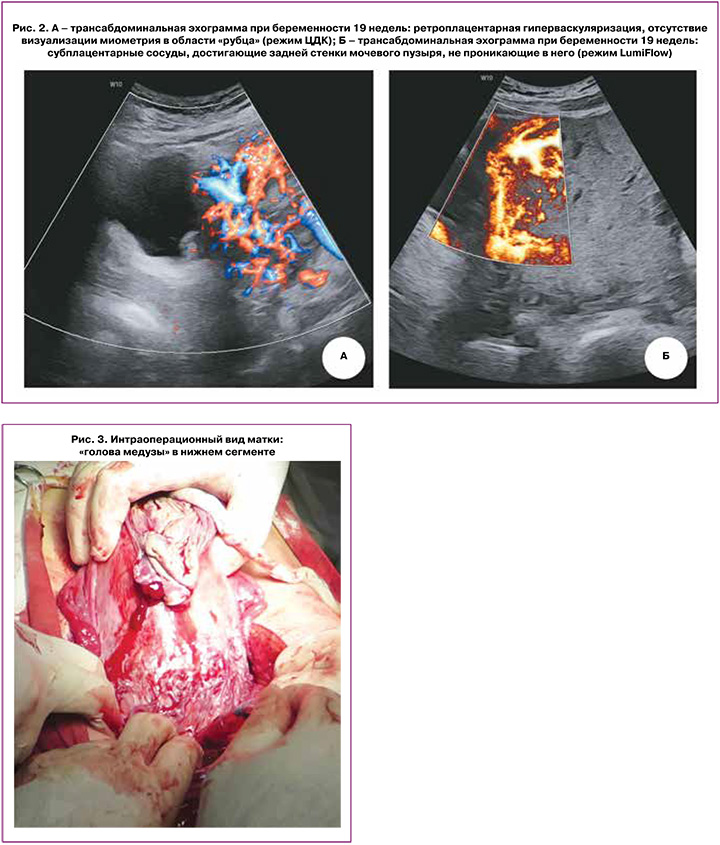

При дальнейшей эхографии, выполненной в отделении ультразвуковой диагностики НИИАП РостГМУ в сроках 17, 19, 22, 25, 30 недель гестации, заключение об аномальном прикреплении хориона в ранние сроки трансформировалось в формулировку о PAS. Так, в сроке 19 недель описано следующее: плацента перекрывает область внутреннего зева, располагаясь по передней стенке матки в проекции послеоперационного рубца, слева визуализируются множественные ретроплацентарные лакуны с ламинарным кровотоком, достигающие зоны истонченного миометрия, в режиме ЦДК – гиперваскуляризация, на участке 50 мм в области «рубца» миометрий отчетливо не лоцируется, субплацентарно в режиме стереоскопической визуализации кровотока (LumiFlow) обнаружены сосуды, достигающие задней стенки мочевого пузыря, не проникающие в него (рис. 2 а, б). На основании проведенного исследования сформулировано заключение о предлежании плаценты, осложненном АИП (placenta increta, PAS 3a по версии Jauniaux E. et al. [10]).

В сроке 37+2 недель в плановом порядке беременность была завершена оперативными родами абдоминальным путем. Под эпидуральной анестезией выполнено донное КС. Родилась доношенная девочка массой 2500 г, длиной 38 см с оценкой по Апгар 7/8 баллов. После рождения ребенка без попыток отделения плаценты осмотрены органы малого таза. Идентифицированы признаки АИП – сосудистая «голова медузы» нижней трети передней стенки тела матки (рис. 3). После лигирования внутренних подвздошных и яичниковых артерий с обеих сторон произведена метропластика. Иссечена часть передней стенки матки с плацентой. Тело матки восстановлено непрерывными швами по авторской методике [17]. Кровопотеря составила 1800 мл. Интраоперационно использована система для реинфузии крови (Sell Saver). Гемотрансфузия в послеоперационном периоде не проводилась. На 7-е сутки в удовлетворительном состоянии пациентка была выписана.